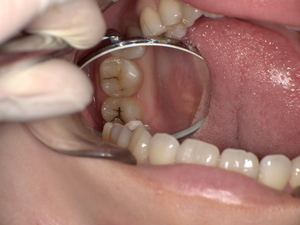

口腔扁平苔癬の主な症状|痛み・赤み・白斑などの見分け方

初期症状と進行症状の違い

初期:細かい白い網目状、軽度のかゆみや違和感

中期〜進行期:白板形成、赤み、潰瘍、強い痛み、出血などが出ることもあります。

他の病気(カンジダ症・白板症)との違い

口腔カンジダ症:ベタつく白い膜を布でこすると取れる。口臭や味覚異常も強い。

口腔白板症:剥離できない白斑で、発がんリスクあり。

口腔扁平苔癬:網目状・線状の病変が特徴。ピリピリとした痛みや焼ける感じがあるのが特徴です。